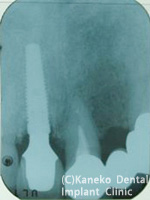

術後のX-P

3年以上経過したが、問題ない。 |